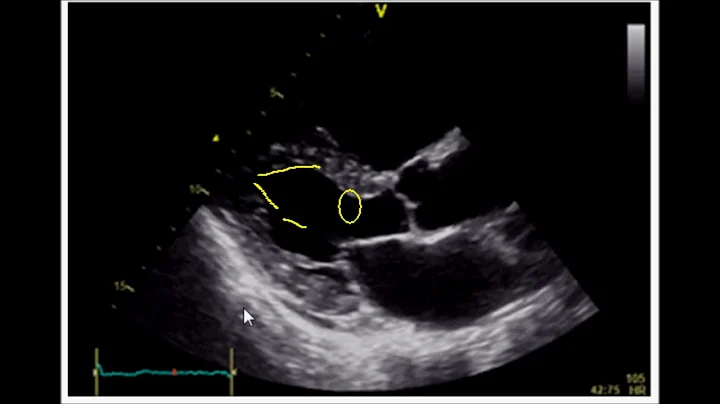

Estimating Ejection Fraction Using Fractional Shortening With Cardiac Ultrasound/echocardiography

Learn how to estimate Left Ventricular Ejection Fraction of the Heart using Fraction Shortening with Cardiac Ultrasound, POCUS, ...